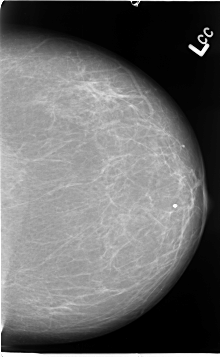

B_3067_1.LEFT_CC

LEFT_CC LINES 4632 PIXELS_PER_LINE 2848 BITS_PER_PIXEL 12 RESOLUTION 50 NON_OVERLAY